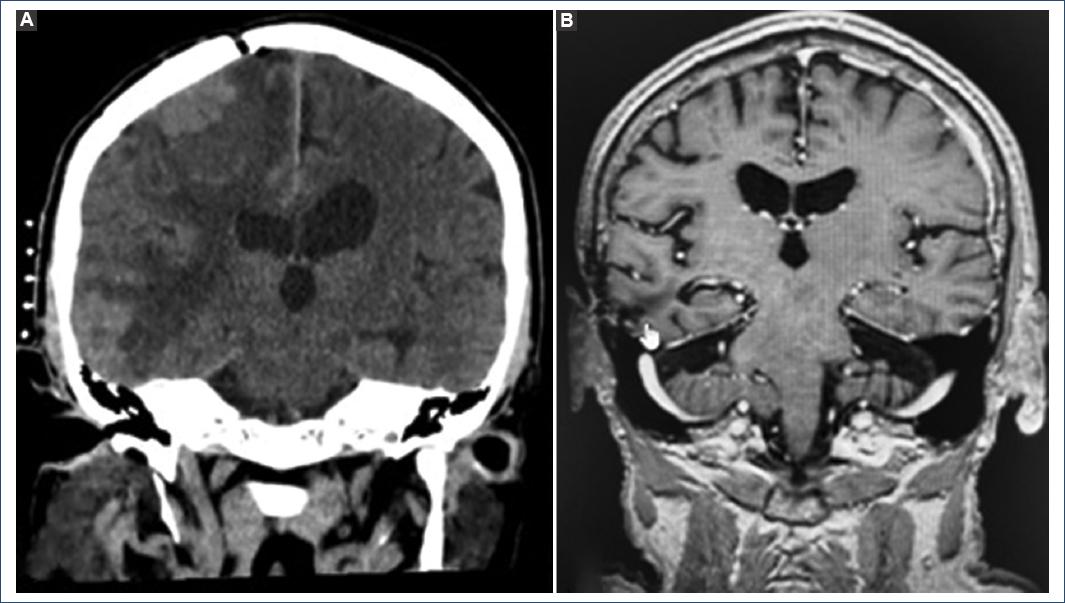

In the 4-year follow-up, there is no evidence of disease progression, the epilepsy is controlled, and the size of the tumor lesions has remained stable. To date, the patient has completed 51 cycles of immunotherapy with nivolumab without complications (Figs. 4 and 5).

Figure 4 A: simple computed axial tomography in coronal section, right temporal lesion enlarged with perilesional edema. B: magnetic nuclear resonance in coronal section post-operative T1 sequence at the second surgical stage, total resection of the right temporal lesion.